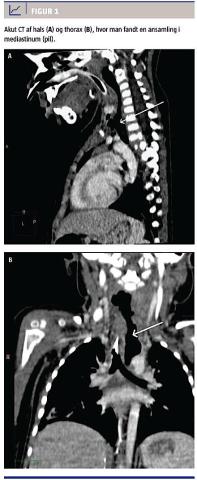

Efter to døgn var der klinisk forværring med hævelse på forsiden af halsen og mistanke om subkutant emfysem, en stigning i C-reaktivt proteinniveauet til 256 mg/l og et leukocytniveau på 27 × 109/l. Der blev foretaget akut CT af hals og thorax, hvor man fandt en ansamling i mediastinum (Figur 1). Ved efterfølgende endoskopi fandt man perforation lige ved indgangen til øsofagus og ned på venstre side, med adgang til en fibrinbelagt, luftfyldt kavitet i media-

stinum. Der blev anlagt ernæringssonde og nasokavitært dræn til sug, og intet per os. De følgende dage bedredes den kliniske tilstand, og infektionstallene blev normaliseret. En afsluttende CT viste en fuldstændig regredieret kavitet i mediastinum. Pigen blev udskrevet til hjemmet i tiltagende trivsel efter 43 dages indlæggelse.